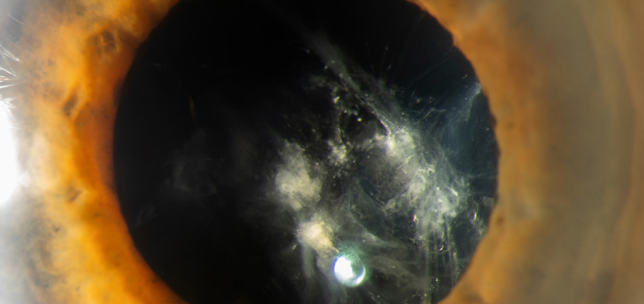

The ANTerior Segment Imaging Competition from Eye News and Keeler promotes and celebrates the work of slit-lamp imaging, culminating in cash prizes and exposure for its winners.

After a successful run in 2024, the ANTS Imaging Competition returned this year with another overwhelming response and our judges were thrilled to have so many amazing images to choose from. We would like to offer a huge congratulations to our winners, honorary mentions, and shortlisted entries, all of which can be seen below. So, without further ado, here some of the best ophthalmic imagers, optometrists and allied professionals in the UK right now: